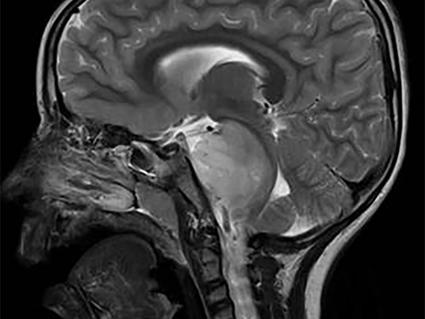

All but one of those 17 patients responded to larotrectinib, including several who had complete responses. One of the complete responses occurred in a child with glioblastoma, a highly fatal type of brain cancer. At the last follow-up point, many of the tumor responses were ongoing, including several that had lasted for more than a year.